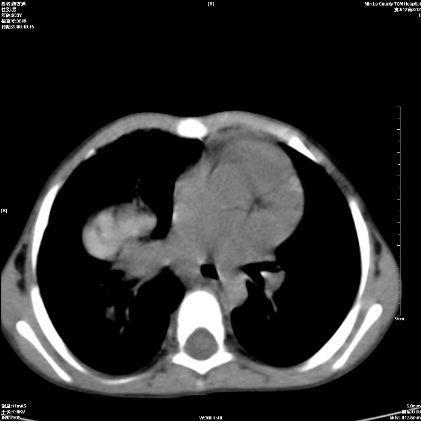

标题: PED1609:男性,3岁。彩超示肝Ca. [打印本页]

标题: PED1609:男性,3岁。彩超示肝Ca.

考虑后纵隔恶性畸胎瘤伴肝内多发转移可能性大,右侧肾上腺转移不除外.

3岁;肝低密度灶;有钙化;有转移灶;考虑肝母细胞瘤;查afp

考虑神经母细胞瘤并肝转移

考虑:1、右侧后下纵隔畸胎瘤。

2、肝脏多发血管内皮细胞瘤。

建议:增强确诊。